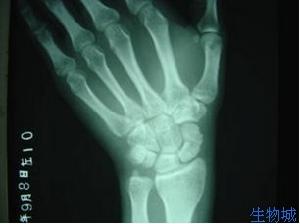

2.X線攝正側斜位片。有時早期骨折線顯示不清可在兩周后再攝片以便確診。

傷後局部腫脹,疼痛,腕關節活動受限並疼痛加重。鼻咽窩處及舟骨結節處有壓痛。第2、3掌骨頭縱向叩擊痛。有時輕微骨折症狀不明顯,與腕扭傷症狀相似,易誤診忽略,腕關節正位、側位、斜位(舟狀位)三種方位X片可確診骨折部位及方向。若骨折不清楚,臨床症狀懷疑骨折時,應暫按骨折處理,待二周后,複查X片。由於骨折處骨質吸收,骨折線能明顯認出。

傷後腕部橈側腫脹疼痛,腕關節活動時疼痛加劇並受限。鼻咽窩及舟骨結節處有明顯壓痛。腕關節橈偏,沿Ⅰ、Ⅱ掌骨長軸叩擊或擠壓時均引起骨折處疼痛。X線片需攝腕關節正、側位及舟骨位三個方向,多能顯示骨折線。有時沒有移位的骨折,早期X線片為陰性。對可疑病例,應在兩周后再照片複查,因傷後骨折處骨質吸收,骨折線增寬而顯出。陳舊性骨折,可見骨折線明顯增寬,骨折端硬化或囊性變,這是骨不連線的表現,若近段骨塊密度增加、變形等則為缺血性壞死。

舟骨骨折按骨折發生的部位分為舟骨中段骨折、近段骨折和結節部骨折。舟骨骨折的骨折線如錯位不明顯時,須留意下列可提示診斷的徵象:①舟骨結節的骨皮質斷裂;②舟骨結節部或頭舟關節間隙內的小游離骨折片;③舟骨一側或雙側關節面骨皮質出現中斷或有垂直於關節面的細小裂隙、皺摺、台階樣改變。